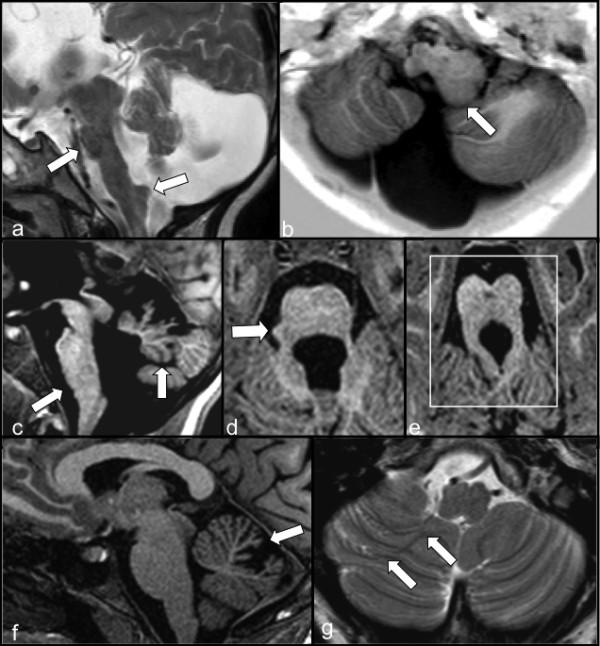

Seventeen patients were molecularly diagnosed in the course of this study and five of these represent new mutations never reported before. Among patients displaying neurological symptoms and/or cognitive/behavioral abnormalities, we identified brain structural anomalies in 88.7%, cognitive impairment in 68%, and associated neurological disorders and signs in 53% of cases. The most frequently observed brain structural anomalies included agenesis of the corpus callosum and neuronal migration/organisation disorders as well as intracerebral cysts, porencephaly and cerebellar malformations.

在本研究过程中对17例患者进行了分子诊断,其中5例代表以前从未报道过的新突变。在出现神经症状和/或认知/行为异常的患者中,我们发现88.7%的患者存在脑结构异常,68%的患者存在认知障碍,53%的病例存在相关的神经系统疾病和体征。最常观察到的脑结构异常包括胼胝体发育不全、神经元迁移/组织紊乱以及脑内囊肿、孔洞脑和小脑畸形。